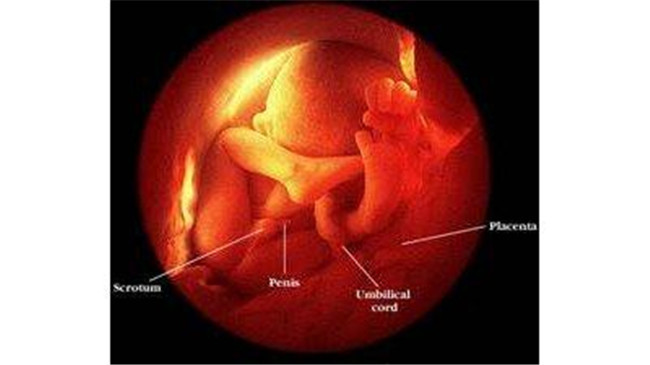

在八个月时,胎儿男婴的*丸睾**已经从腹腔下降落入了他的阴囊内,但是有的男婴的*丸睾**是出生当天才进入阴囊的,有的因为发育迟缓问题,出生后还没有进入的,就要进行治疗了。

胎儿这个时候的指甲已经长出来了挺长的,皮肤是淡红色,比较光滑,但脸仍然充满皱纹。

宝宝能够在子宫里转来转去。胎儿现在长得越来越大,孕后期是胎儿增长最快的时候,身体几乎占据了整个子宫,所以胎动会逐渐的减少。

身长已经达到40到45厘米,体重增长到1400到2100克,已经具备了在子宫外生活的能力,但是仍然要注意,因为肺部还没发育完全,所以这个时期需要保重身体,避免早产。